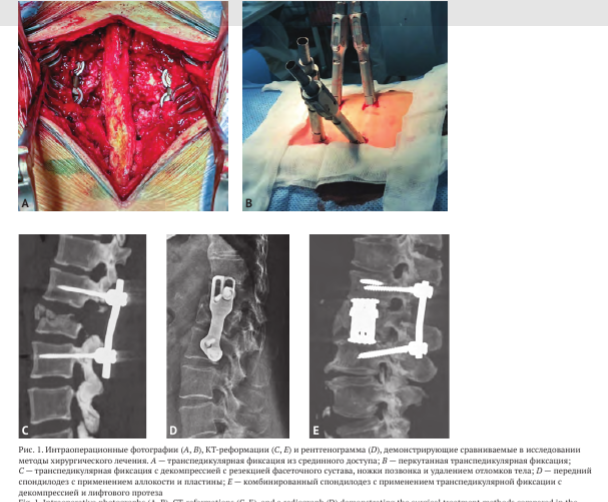

Все проведённые операции мы разделили на шесть групп в зависимости от доступа и факта выполнения декомпрессии: изолированная транспедикулярная фиксация из срединного доступа (срТПФ); перкутанная ТПФ (пТПФ); ТПФ с декомпрессией ПК в виде ламинэктомии с или без удаления костных отломков тела позвонка (декТПФ); передняя декомпрессия и спондилодез с применением пластин; комбинированное вмешательство (ТПФ и передний спондилодез с применением различных трансплантатов) с или без вмешательства в просвет ПК (рис. 1).